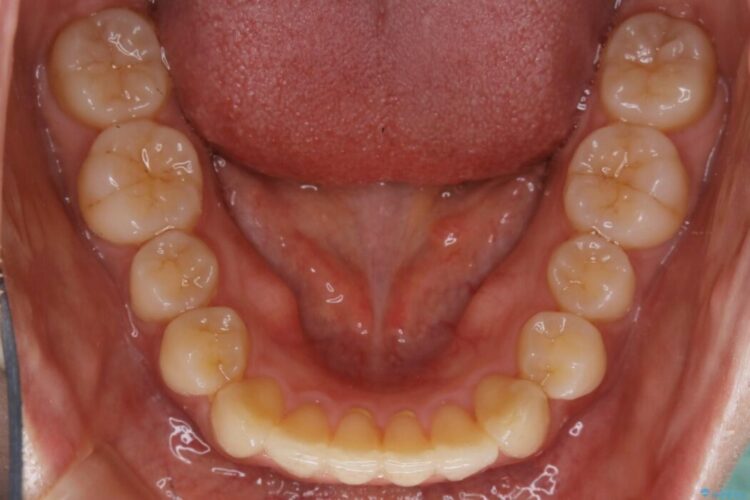

下額前歯が少しガタついていることを気にされて来院されました。

検査をしたところ奥歯の噛み合わせなどに問題が見られなかったため、軽度のねじれがある下顎前歯に焦点を当てた部分矯正の適応が可能と判断し、インビザラインのライトパッケージをご提案しました。